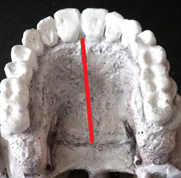

Figure 1 Image of a Le Fort 1 osteotomy line is inserted with its modification by performing an osteotomy in the intermaxillary suture.

Figure 2 Image showing the osteotomy line in the intermaxillary suture to create disjunction of the palate.